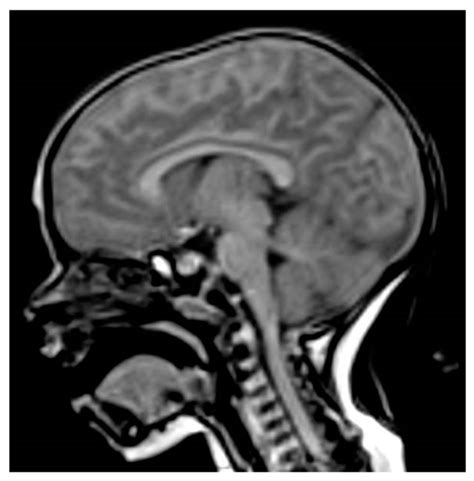

The pituitary gland, often referred to as the "master gland," plays a critical role in regulating numerous bodily functions by releasing essential hormones. Because of its small size and strategic location at the base of the brain, identifying abnormalities within it requires specialized diagnostic tools. A pituitary gland MRI (Magnetic Resonance Imaging) is the gold-standard imaging technique used by physicians to visualize this complex structure in high detail. By utilizing strong magnetic fields and radio waves, this non-invasive test provides clear images that help doctors diagnose conditions ranging from benign tumors to hormonal imbalances.

When patients present with symptoms related to hormonal dysregulation, a healthcare provider may order imaging to investigate the pituitary gland. This gland sits within a bony structure called the sella turcica. Because this area is quite intimate, standard brain scans may not always offer the resolution required to see micro-adenomas—very small tumors that can significantly affect hormone production. A dedicated pituitary gland MRI focuses specifically on this region, ensuring that even minute structural changes are identified.

Once the images are acquired, they are sent to a radiologist—a doctor who specializes in medical imaging. The radiologist carefully reviews the scans for any signs of enlargement, masses, or structural abnormalities within the pituitary gland or the surrounding tissues, such as the optic chiasm. The findings are documented in a comprehensive report, which is then sent to the physician who ordered the scan. Your doctor will then correlate these findings with your blood work and clinical symptoms to determine the next steps in your care.